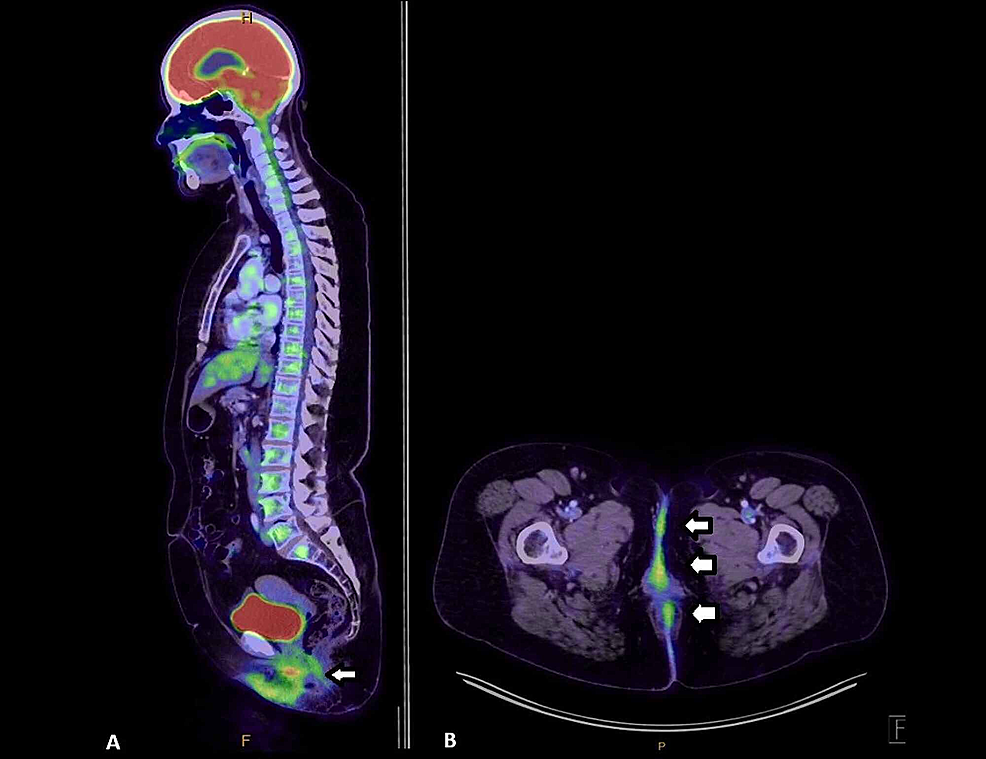

Cureus Extensive Extramammary Paget’s Disease With Underlying

From www.cureus.com

Extensive Extramammary Paget’s Disease With Underlying Perianal Paget's Disease Radiation Therapy This systematic review investigates the role of radiotherapy and its best technical profile in the treatment of this disease, with great attention. Radiotherapy was administered as postoperative adjuvant treatment in 9 articles with doses ranging between 32 and 64.8 gy in 20 to 30. [1] complete surgical removal of localized disease. Sir james paget described an intraepidermal neoplasm of the. Paget's Disease Radiation Therapy.

Cureus Extensive Extramammary Paget’s Disease With Underlying Paget's Disease Radiation Therapy Sir james paget described an intraepidermal neoplasm of the mammary areola in 1874, and it was subsequently named paget's disease (1). This systematic review investigates the role of radiotherapy and its best technical profile in the treatment of this disease, with great attention. Extramammary paget's disease (empd) is a relatively rare malignancy, and there are few reports related to radiation. Paget's Disease Radiation Therapy.

Cureus Extensive Extramammary Paget’s Disease With Underlying Paget's Disease Radiation Therapy Radiotherapy was administered as postoperative adjuvant treatment in 9 articles with doses ranging between 32 and 64.8 gy in 20 to 30. Extramammary paget's disease (empd) is a relatively rare malignancy, and there are few reports related to radiation therapy. When invasive extramammary paget disease (empd) metastasizes to distant sites as well as in case of wide locoregional disease that. Paget's Disease Radiation Therapy.